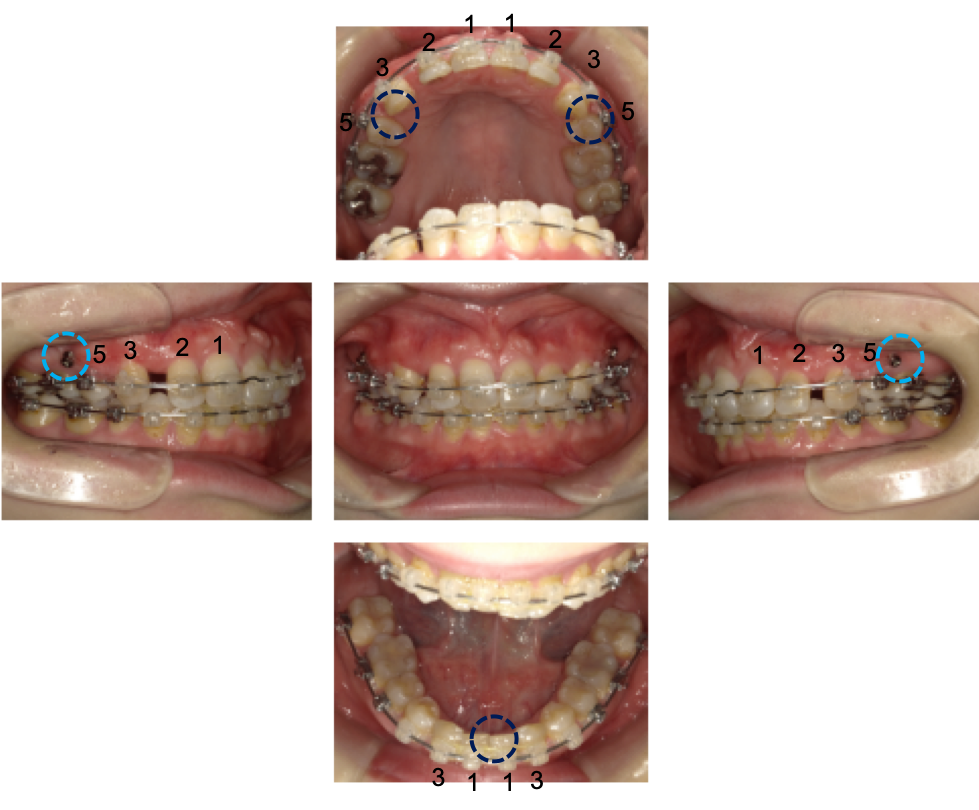

下顎は、生まれつき下の前歯が1本欠如している「スリーインサイザー(3 incisor)」の状態でした。下の2番の歯が無いことがわかります。

※青色の番号…抜歯箇所です

上顎の左右4番の歯を抜いたあと、3番の歯をうしろへ動かしました。

その結果、3番の歯は5番の歯のすぐ隣まで移動し、2番と3番の歯の間にすき間ができています。口ゴボを改善するため左右1番2番を後ろへ下げました。

下顎左2番を抜歯し、左右1番が中心線に揃うようにしました。

・紺色の丸部分…抜歯した箇所

・水色の矢印部分…アンカースクリュー>>です。